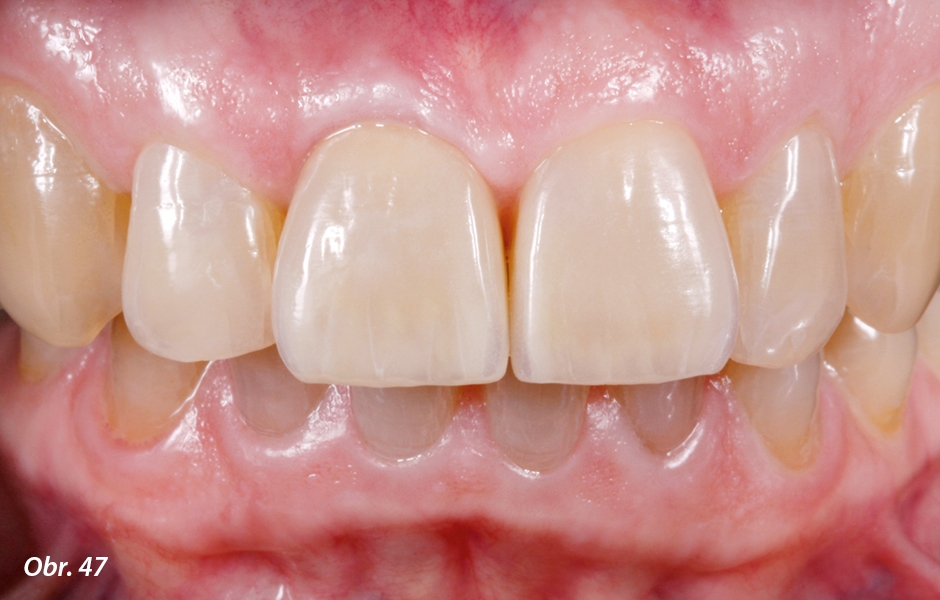

U obou rekonstrukcí je po dvou týdnech od nasazení patrna dobrá funkční i estetická integrace

Po sejmutí provizorní korunky z implantátu byla patrna zdravá marginální gingiva s perfektní oporou měkkých periimplantárních tkání způsobenou individuálním hybridním abutmentem jak ve vertikálním (obr. 45), tak i v horizontálním směru (obr. 46). Otvor pro šroubek abutmentu byl uzavřen pomocí teflonové pásky a kompozitu. Při přípravě na definitivní fixaci zirkonoxidové korunky na abutment bylo velice opatrně cirkulárně okolo abutmentu zavedeno tenké retrakční vlákno a následně byla definitivně nasazena korunka vyplněna samoadhezivním, duálně tuhnoucím fixačním kompozitem.28 Dva týdny po fixaci korunky na implantát vykazovaly obě rekonstrukce dobrou funkční i estetickou integraci do zubního oblouku (obr. 47–51). I v kombinaci se rty působí celá protetická práce velice harmonicky (obr. 52–54). Pod UV světlem je patrna přítomná fluorescence obou rekonstrukcí, jež se však neliší od přirozených tvrdých zubních tkání (obr. 55). Závěrečný rentgenový snímek ukázal dobrou a stabilní oseointegraci implantátu (obr. 56). Pacientka byla s výsledkem ošetření zcela spokojena (obr. 57).